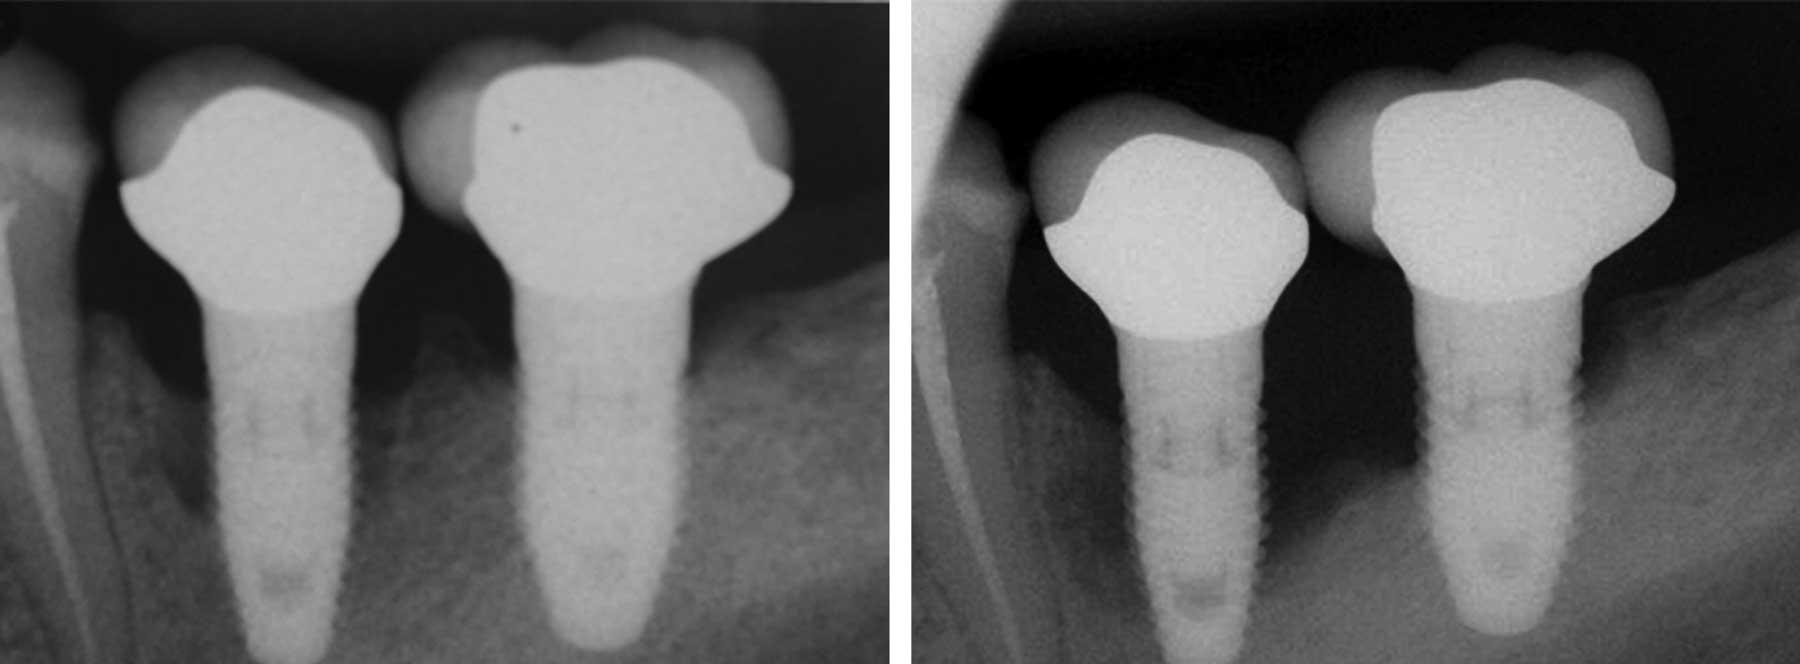

Peri-implant disease is an inflammatory condition affecting the tissue around dental implants. Bacteria can build up and over time irritates the gum tissue, leading to irritation and damage. Without intervention, it will cause the bone structure below the implant to deteriorate.

A radiograph two years after implant placement, then seven years later in a heavy smoker, demonstrating progression of bone loss due to peri-implantitis. Source: Wikipedia

There is currently no one treatment that yields consistently successful results, but stem-cell and other regenerative techniques look promising. There is a consistent emphasis on the importance of preventing the condition in the first place and/or keeping it from getting worse. Medication changes and regular dental appointments are crucial.